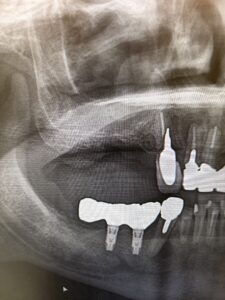

インプラント症例がありましたのでご紹介。

40代男性。当院で3回目のインプラント。

右上に2本埋入しました。